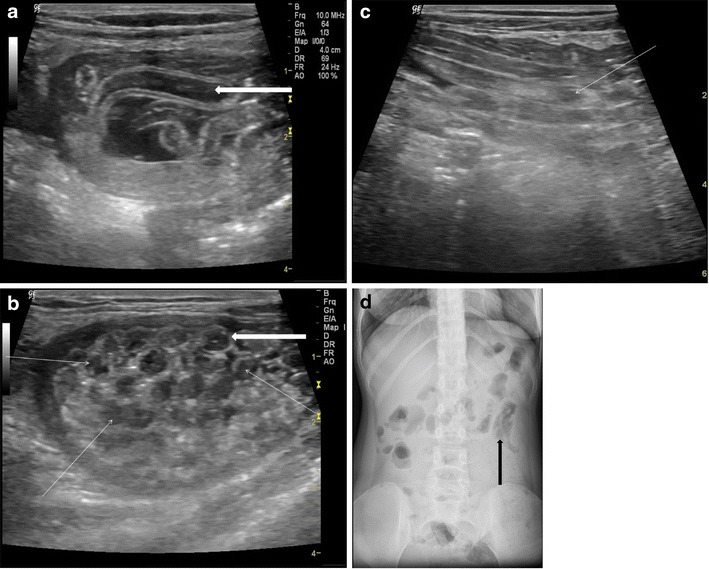

Adult worms are seen as tubular structures outlined by intestinal fluid. The adult worm is seen as a large, curved echogenic strip with an inner, anechoic, longitudinal canal [3]. When we used a high-resolution linear (7–10 mhz) transducer (Logiq P5, GE Milwaukee US), in long section the worm appeared as four parallel lines separated by three anechoic bands (Fig. 1a). In cross section, it is round and sometimes appearing as a “target sign” [4]. The live worms are sometimes seen moving in the intestinal lumen. At times they are multiple forming a bag or cluster of worms, which can cause intestinal obstruction (Fig.1b&c). On rare occasions, the round worm can also be seen in a plain x-ray abdomen (Fig. 1d).

Fig. 1.

A 25-year-old female with acute abdomen and clinical signs of intestinal obstruction. (a) High resolution ultrasound using linear array transducer showing intestinal ascariasis, note distended fluid filled alimentary canal of the ascaris (thick white arrow), the “inner tube sign”, (b) same patient showing multiple ring like shadows (thin white arrows), some with target appearance (thick white arrow) on transverse section of the intestinal lumen indicating bag of worms, (c) “Bag of worms” in a long section (thin white arrow) and (d) PA erect X-ray abdomen of this patient showing tubular soft densities suggestive of ascariasis (thick black arrow)